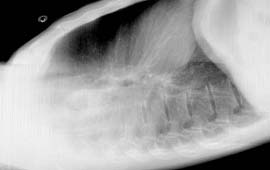

(4)胸部X線檢查:肺部有不同程度的片狀、斑片狀浸潤性陰影或呈網狀改變,部分患者進展迅速,呈大片狀陰影;常為多葉或雙側改變,陰影吸收消散較慢;肺部陰影與症狀體徵可不一致。若檢查結果陰性,1~2天后應予複查。

其他輔助檢查:影像學檢查:絕大部分患者在起病早期即有胸部X線檢查異常,多呈斑片狀或網狀改變。起病初期常呈單灶病變,短期內病灶迅速增多,常累及雙肺或單肺多葉。部分患者進展迅速,呈大片狀陰影。雙肺周邊區域累及較為常見,而胸腔積液、空洞形成以及肺門淋巴結增大等表現則較少見。對於胸片無病變而臨床又懷疑為本病的患者,1~2天內要複查胸部X線檢查。胸部CT檢查以玻璃樣改變最多見。肺部陰影吸收、消散較慢;陰影改變與臨床症狀體徵有時可不一致。